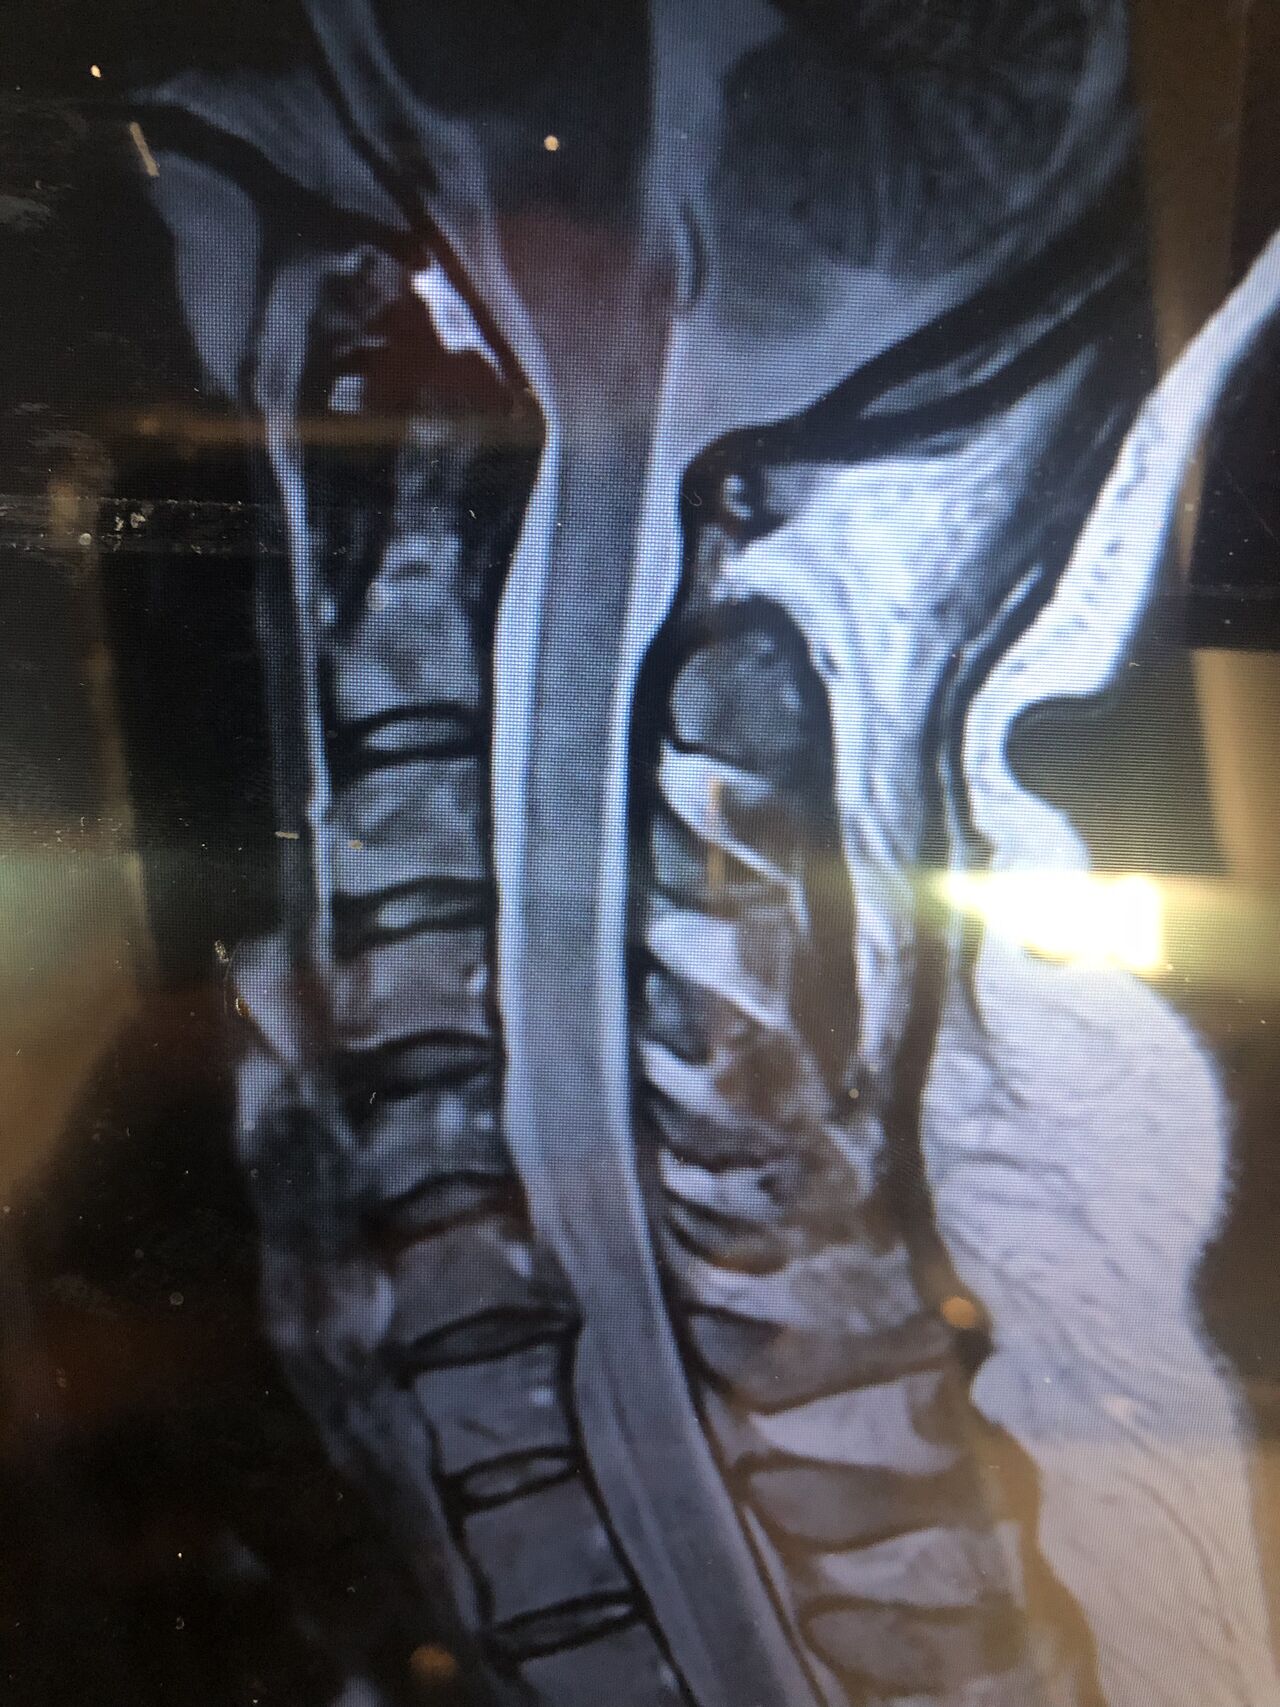

30 year old patient of mine with R. IVF disc extrusion of C 5-6 with R upper extremity pain and numbness without neurological deficit was suggested to have urgent surgery

in his EMG. NCV didn’t have any active axonal loss

got 20 sessions of chiropractic care in one month by me mainly using decompression and C0-C1 prone drop manipulation and 3 sessions of mild adjustment to segments above disc herniation. No direct adjustment to the involved disc extrusion

After treatment:

reduction of R. IVFdisc extrusion by more than 50%.

90% improvement in patient’s signs and symptoms and preventing of unnecessary expensive surgery

following one month of cervical chiropractic spinal treatments